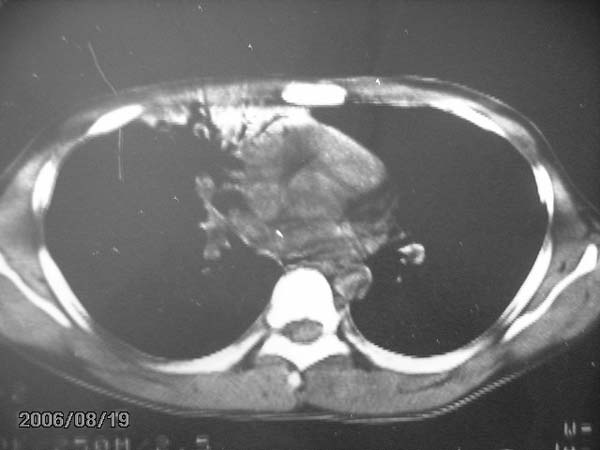

男,13岁,发烧半月,干咳无痰,正规使用抗生素半月,现在仍是午后低烧!!!未做痰检

右侧肺门淋巴结好象有增大,会不会是个原发综合症合并感染

右肺中叶大片状密度增高影,内密度不均匀,右肺门处增大,应该是淋巴结肿大,结合临床首先考虑原发性肺结合可能性大,不排除合并感染可能,建议治疗后复查.

考虑中叶综合征(右肺门肿大淋巴结伴中叶阻塞性炎症)